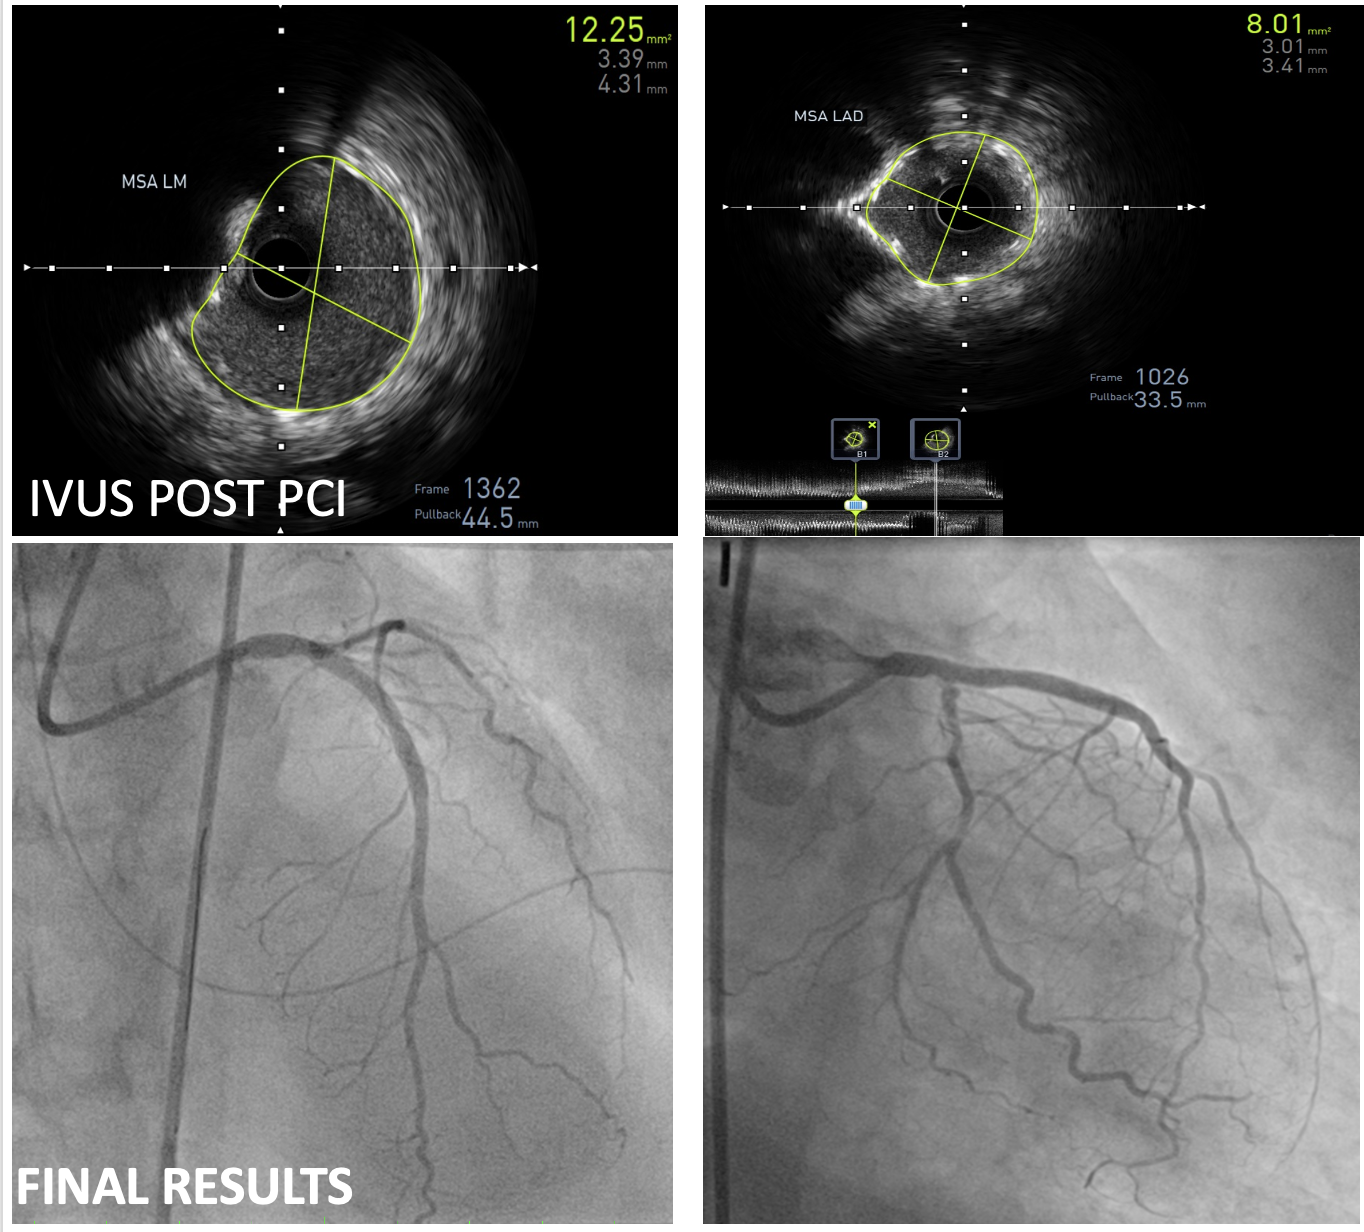

Percutaneous coronary intervention (PCI) of the LMCA-LAD lesion was performed with intra-aortic balloon pump (IABP) support. A 6 French EBU 3.5 guiding catheter was used to engage the left coronary artery. After wiring the lesion with a moderate support wire, intravascular ultrasound (IVUS) revealed an eruptive calcified nodule in the distal LMCA and heavy calcification (270-360 degrees) in the LAD. Rotablation was performed with a 1.5 mm burr for 3 runs. Following rotablation, the LAD wire was lost but successfully rewired. The LMCA-LAD lesion was predilated with a 3.0 x 15 mm non-compliant (NC) balloon. Provisional crossover stenting of the LMCA-LAD was performed with a 3.0 x 38 mm drug-eluting stent (DES). Proximal optimization was achieved with a 4.0 x 8 mm NC balloon inflated to 16 atmospheres (ATM) in the LMCA. The proximal-mid LAD was post-dilated with a 3.0 x 15 mm NC balloon inflated to 12 ATM. Repeat IVUS demonstrated good stent apposition and landing zones with no edge dissection, but the minimal stent area (MSA) in the proximal LAD required further optimization. Final post-dilation in proximal LAD with a 3.5 x 12 mm non-compliant (NC) balloon inflated to 16 ATM resulted in a good final angiographic result and IVUS-confirmed MSA of 8.01 mm2 in the LAD and 12.24 mm2 in the LMCA.

Case Summary